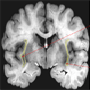

Nissl stain of

coronal section in

human